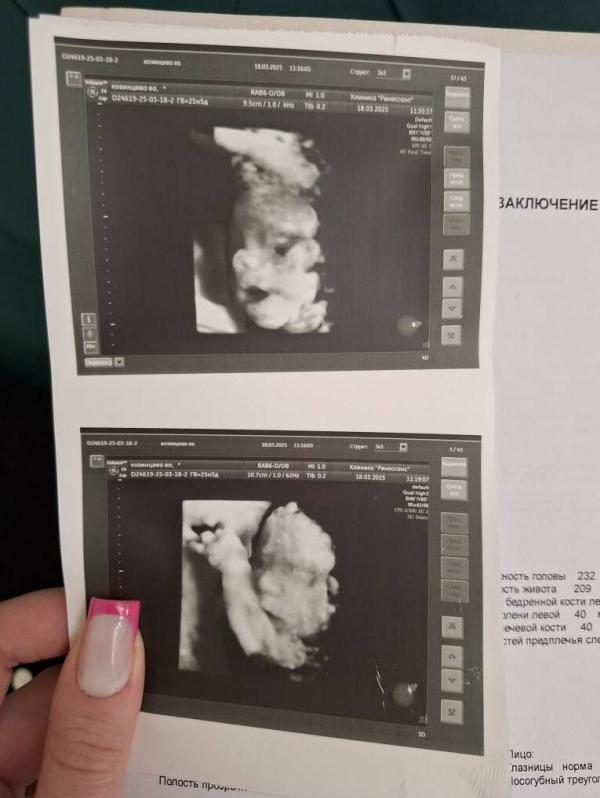

Съездила на 4д узи и увиделась со своим вторым сыном. На фото просто копия мужа и сына. Единственное пока сидим попой вниз.

Но эмоции не передать словами увиденное. Дали еще флешку с видео.

Парень активный, часто пинается. У него все отлично.

У меня шейка 42 мм, плацента поднялась, 3 см от зева.